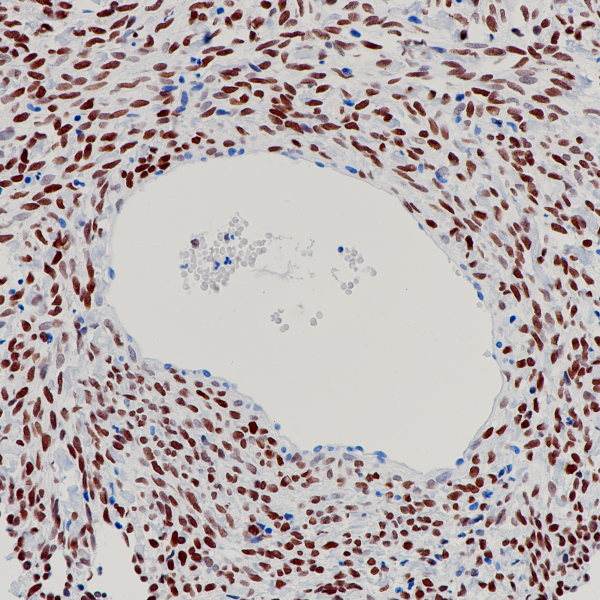

FABP3

BP6313

FOXL2

BP6235

FOXP1

BP6112

FOXP3

BP6166

FRα

BP6286